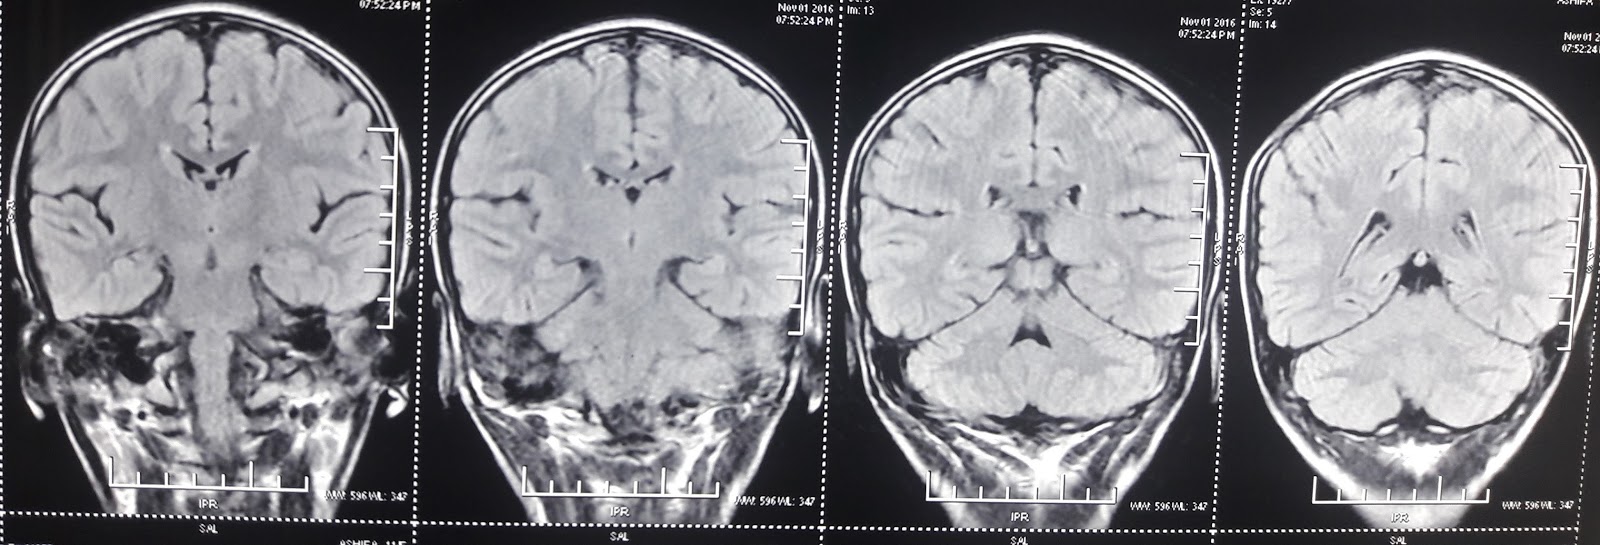

3/11/2016 Repeat MRI done yesterday

But biochemical investigation, MRI did nt support this .